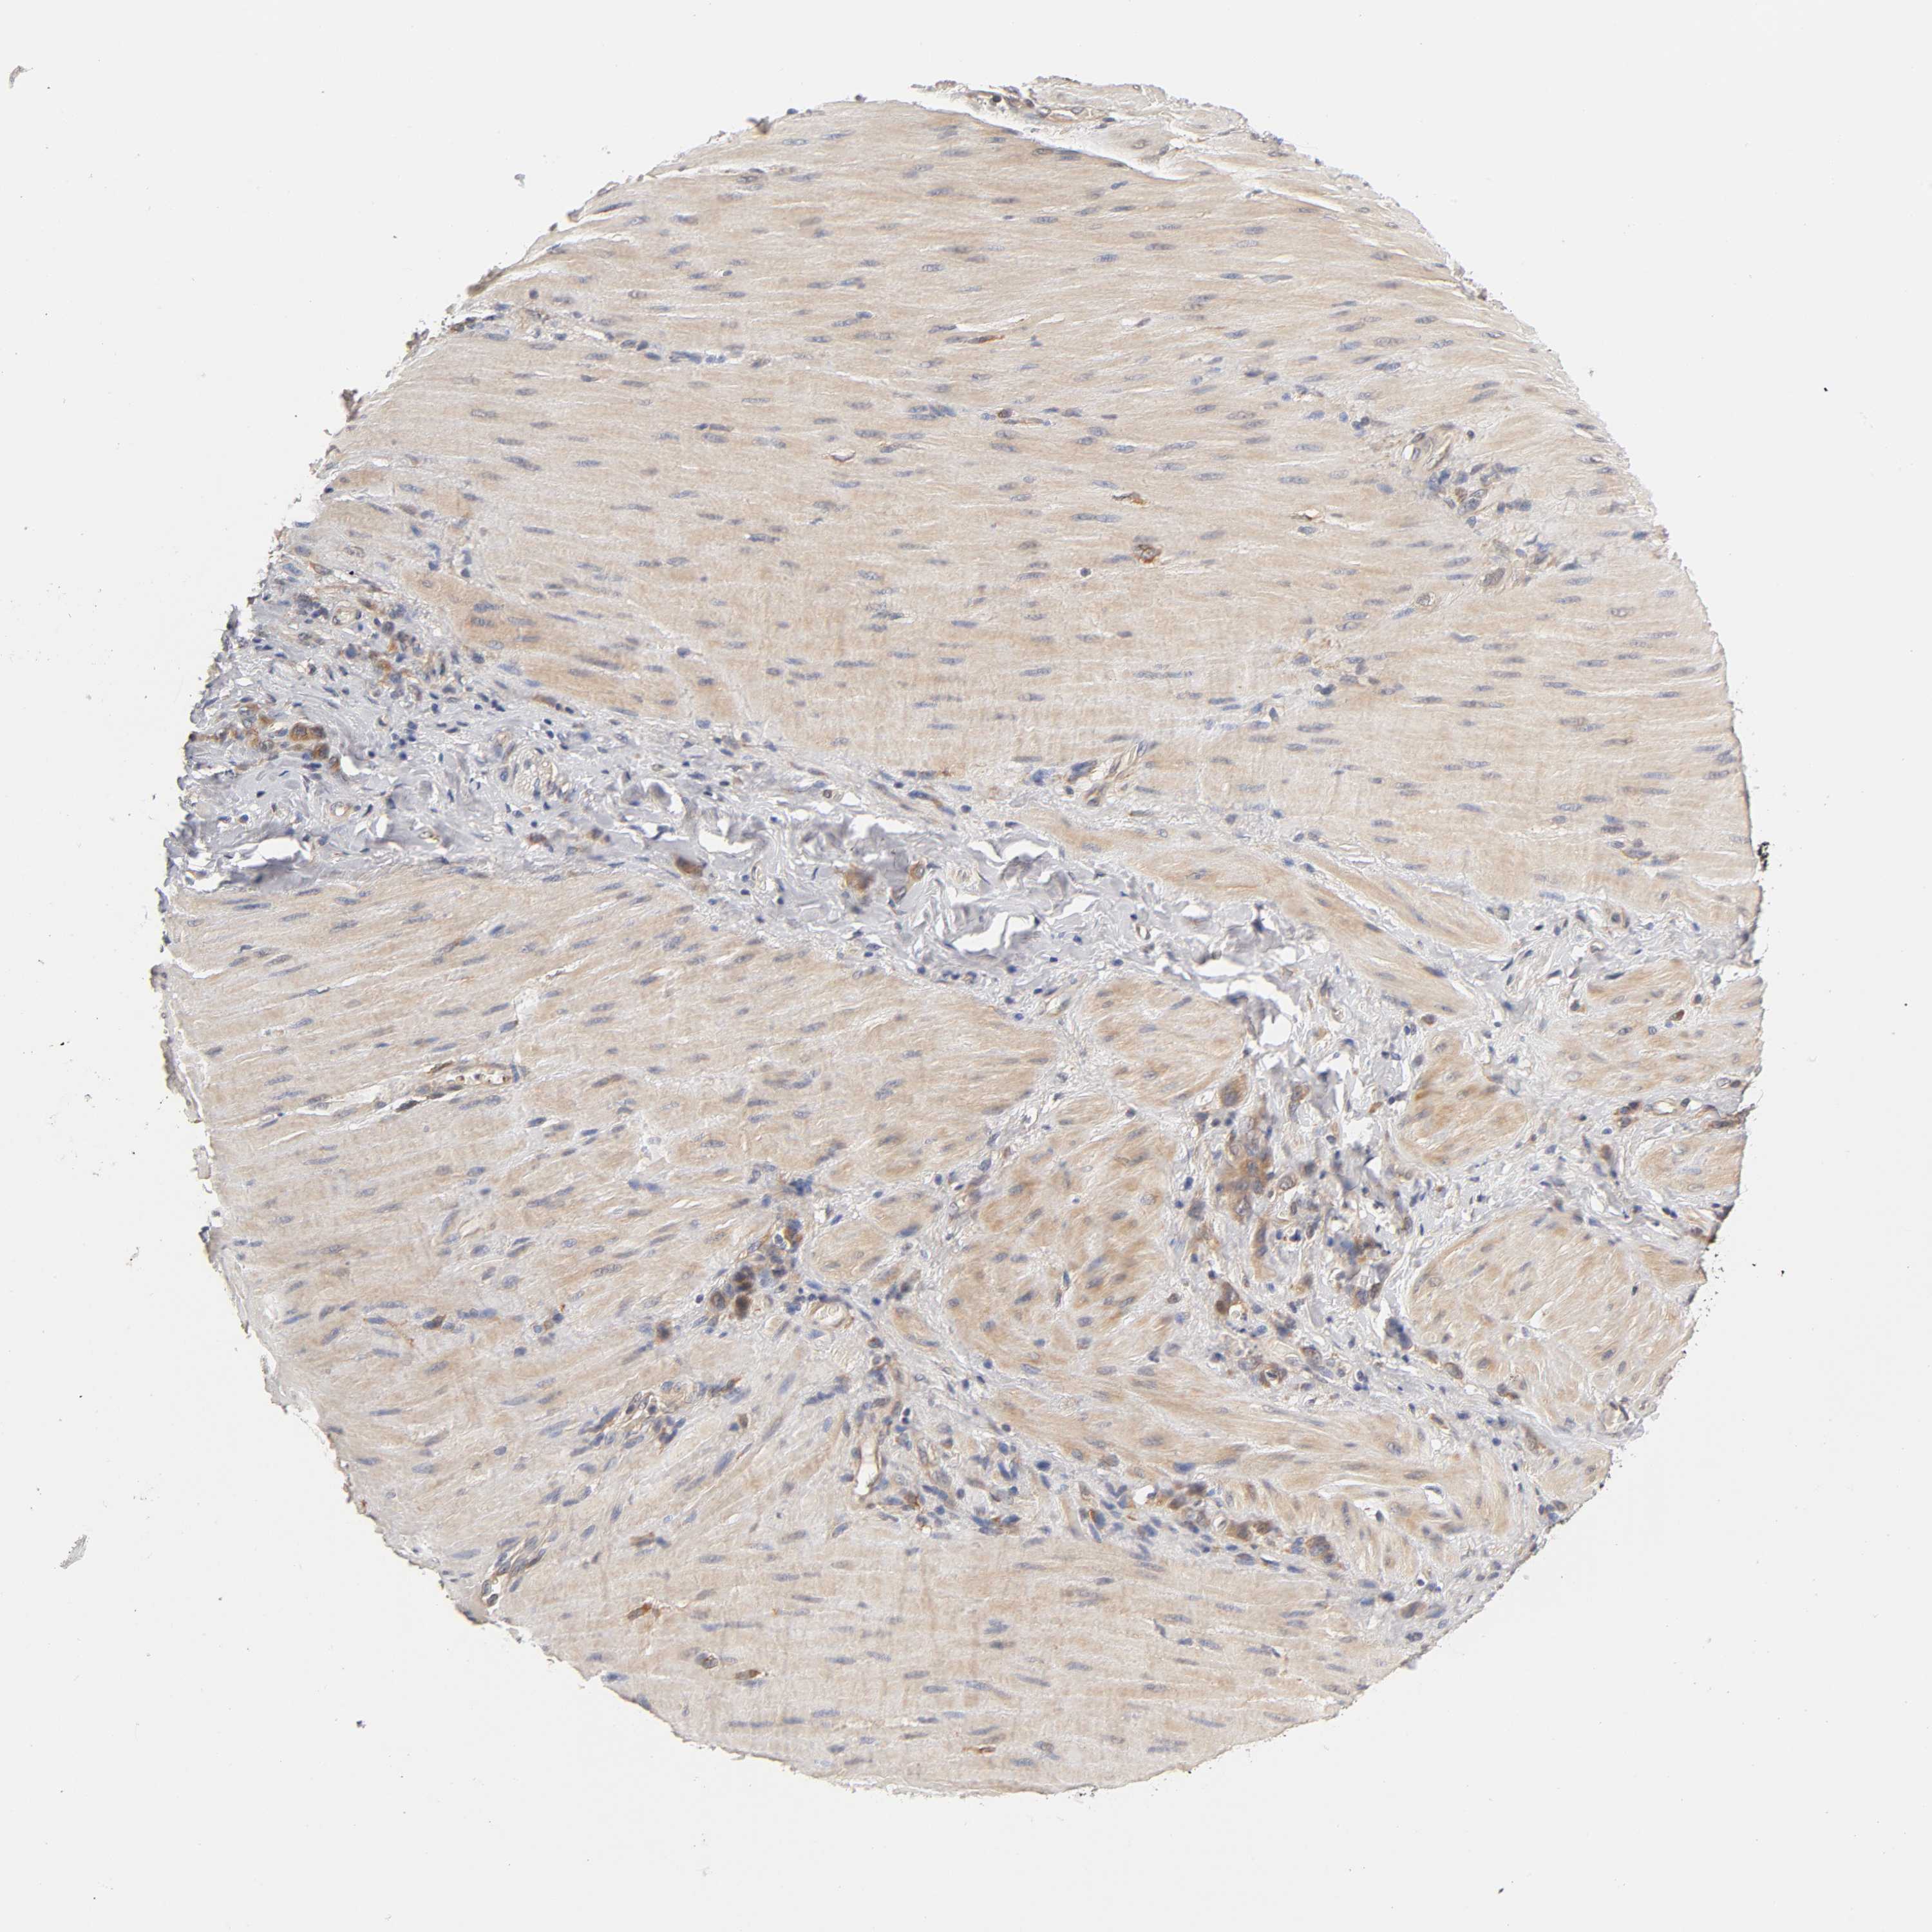

STOMACH CANCER - Protein expressioni

A mouse-over function shows sample information and annotation data. Click on an image to view it in a full screen mode. Samples can be filtered based on level of antibody staining by selecting one or several of the following categories: high, medium, low and not detected. The assay and annotation is described here.

Antibody stainingi

Antibody staining in the annotated cell types in the current human tissue is reported as not detected, low, medium, or high, based on conventional immunohistochemistry profiling in selected tissues. This score is based on the combination of the staining intensity and fraction of stained cells.

Each image is clickable and will lead to virtual microscopy that enables deeper exploration of all samples and also displays staining intensity scores, fraction scores and subcellular localization as well as patient and tissue information for each sample.

Antibody HPA004729

Antibody HPA012873

Staining

High

Medium

Low

Not detected

Intensity

Strong

Moderate

Weak

Negative

Quantity

>75%

75%-25%

<25%

None

Location

Nuclear

Cytoplasmic/membranous

Cytoplasmic/membranous,nuclear

Adenocarcinoma, NOS

Adenocarcinoma, High grade